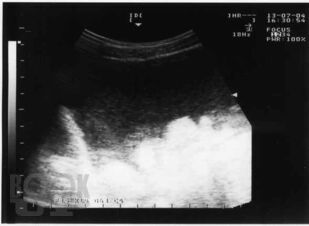

Материалом послужили данные многолетнего обследования больных декомпенсированным циррозом печени, проанализированы клинические проявления спонтанного бактериального перитонита, в том числе системной воспалительной реакции, использован широкий комплекс современных методов: подсчет полиморфноядерных нейтрофилов в асцитической жидкости, микробиологическое исследование крови и асцита, ультразвуковая оценка акустической однородности асцита, исследовано содержание цитокинов, С-реактивного белка, количественный и качественный состав химических компонентов – маркеров потенциальных возбудителей инфекции асцитической жидкости методом газовой хроматографии-масс-спектрометрии. В работе представлены результаты исследования позволяющие диагностировать спонтанный бактериальный перитонит на более ранних сроках, что позволяет проводить своевременную адекватную терапию. Рассмотрены вопросы дифференциальной диагностики первичного и вторичного бактериального перитонита, приведены яркие клинические примеры, отражающие трудности диагностики.

В книге на основе анализа литературы и собственных данных автором представлены современные аспекты этиологии, патогенеза, диагностики, профилактики и лечения спонтанного бактериального перитонита у больных циррозом печени. Материалом послужили данные многолетнего обследования больных декомпенсированным циррозом печени, проанализированы клинические проявления спонтанного бактериального перитонита, в том числе системной воспалительной реакции, использован широкий комплекс современных методов: подсчет полиморфноядерных нейтрофилов в асцитической жидкости, микробиологическое исследование крови и асцита, ультразвуковая оценка акустической однородности асцита, исследовано содержание цитокинов, С-реактивного белка, количественный и качественный состав химических компонентов – маркеров потенциальных возбудителей инфекции асцитической жидкости методом газовой хроматографии-масс-спектрометрии.